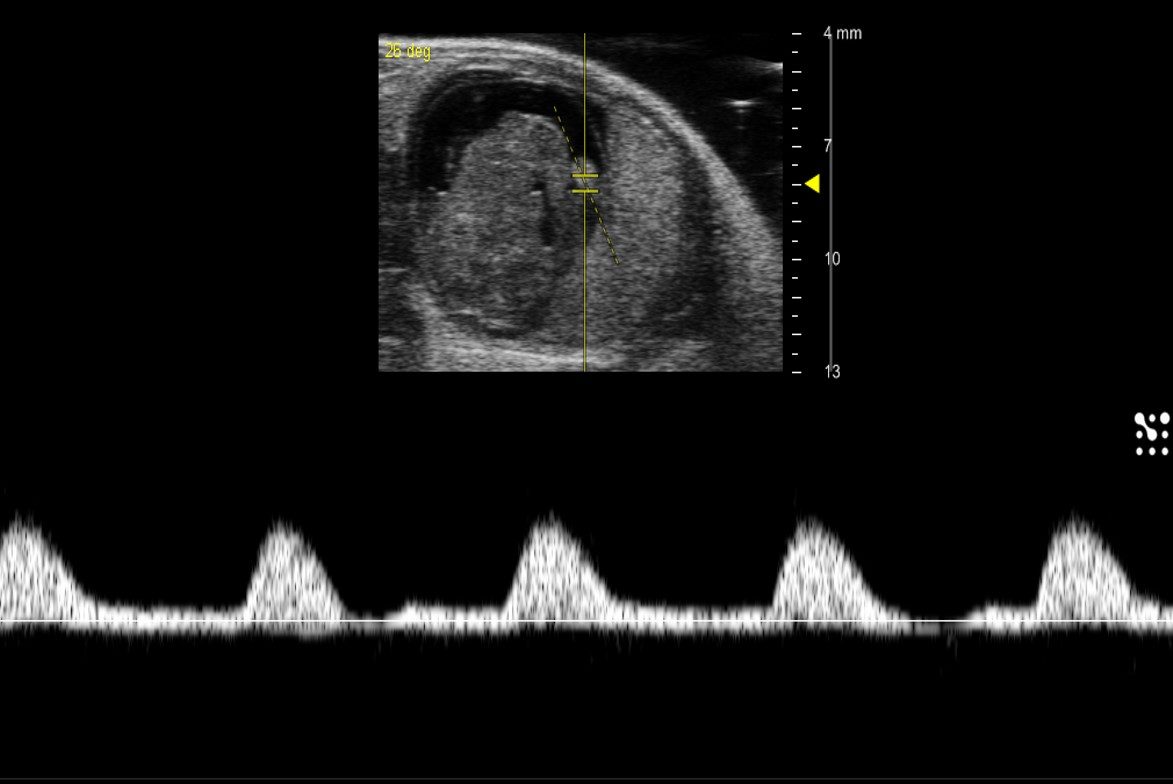

M-mode examines a line of Motion over time. Using M-mode in echocardiography displays the movement of the myocardium allowing for accurate and real-time measurements of wall thickness, internal diameter, and heart rate. It is from these parameters that many systolic parameters are derived (i.e. fractional shortening, ejection fraction, chamber volumes, etc.).

Heart - M Mode